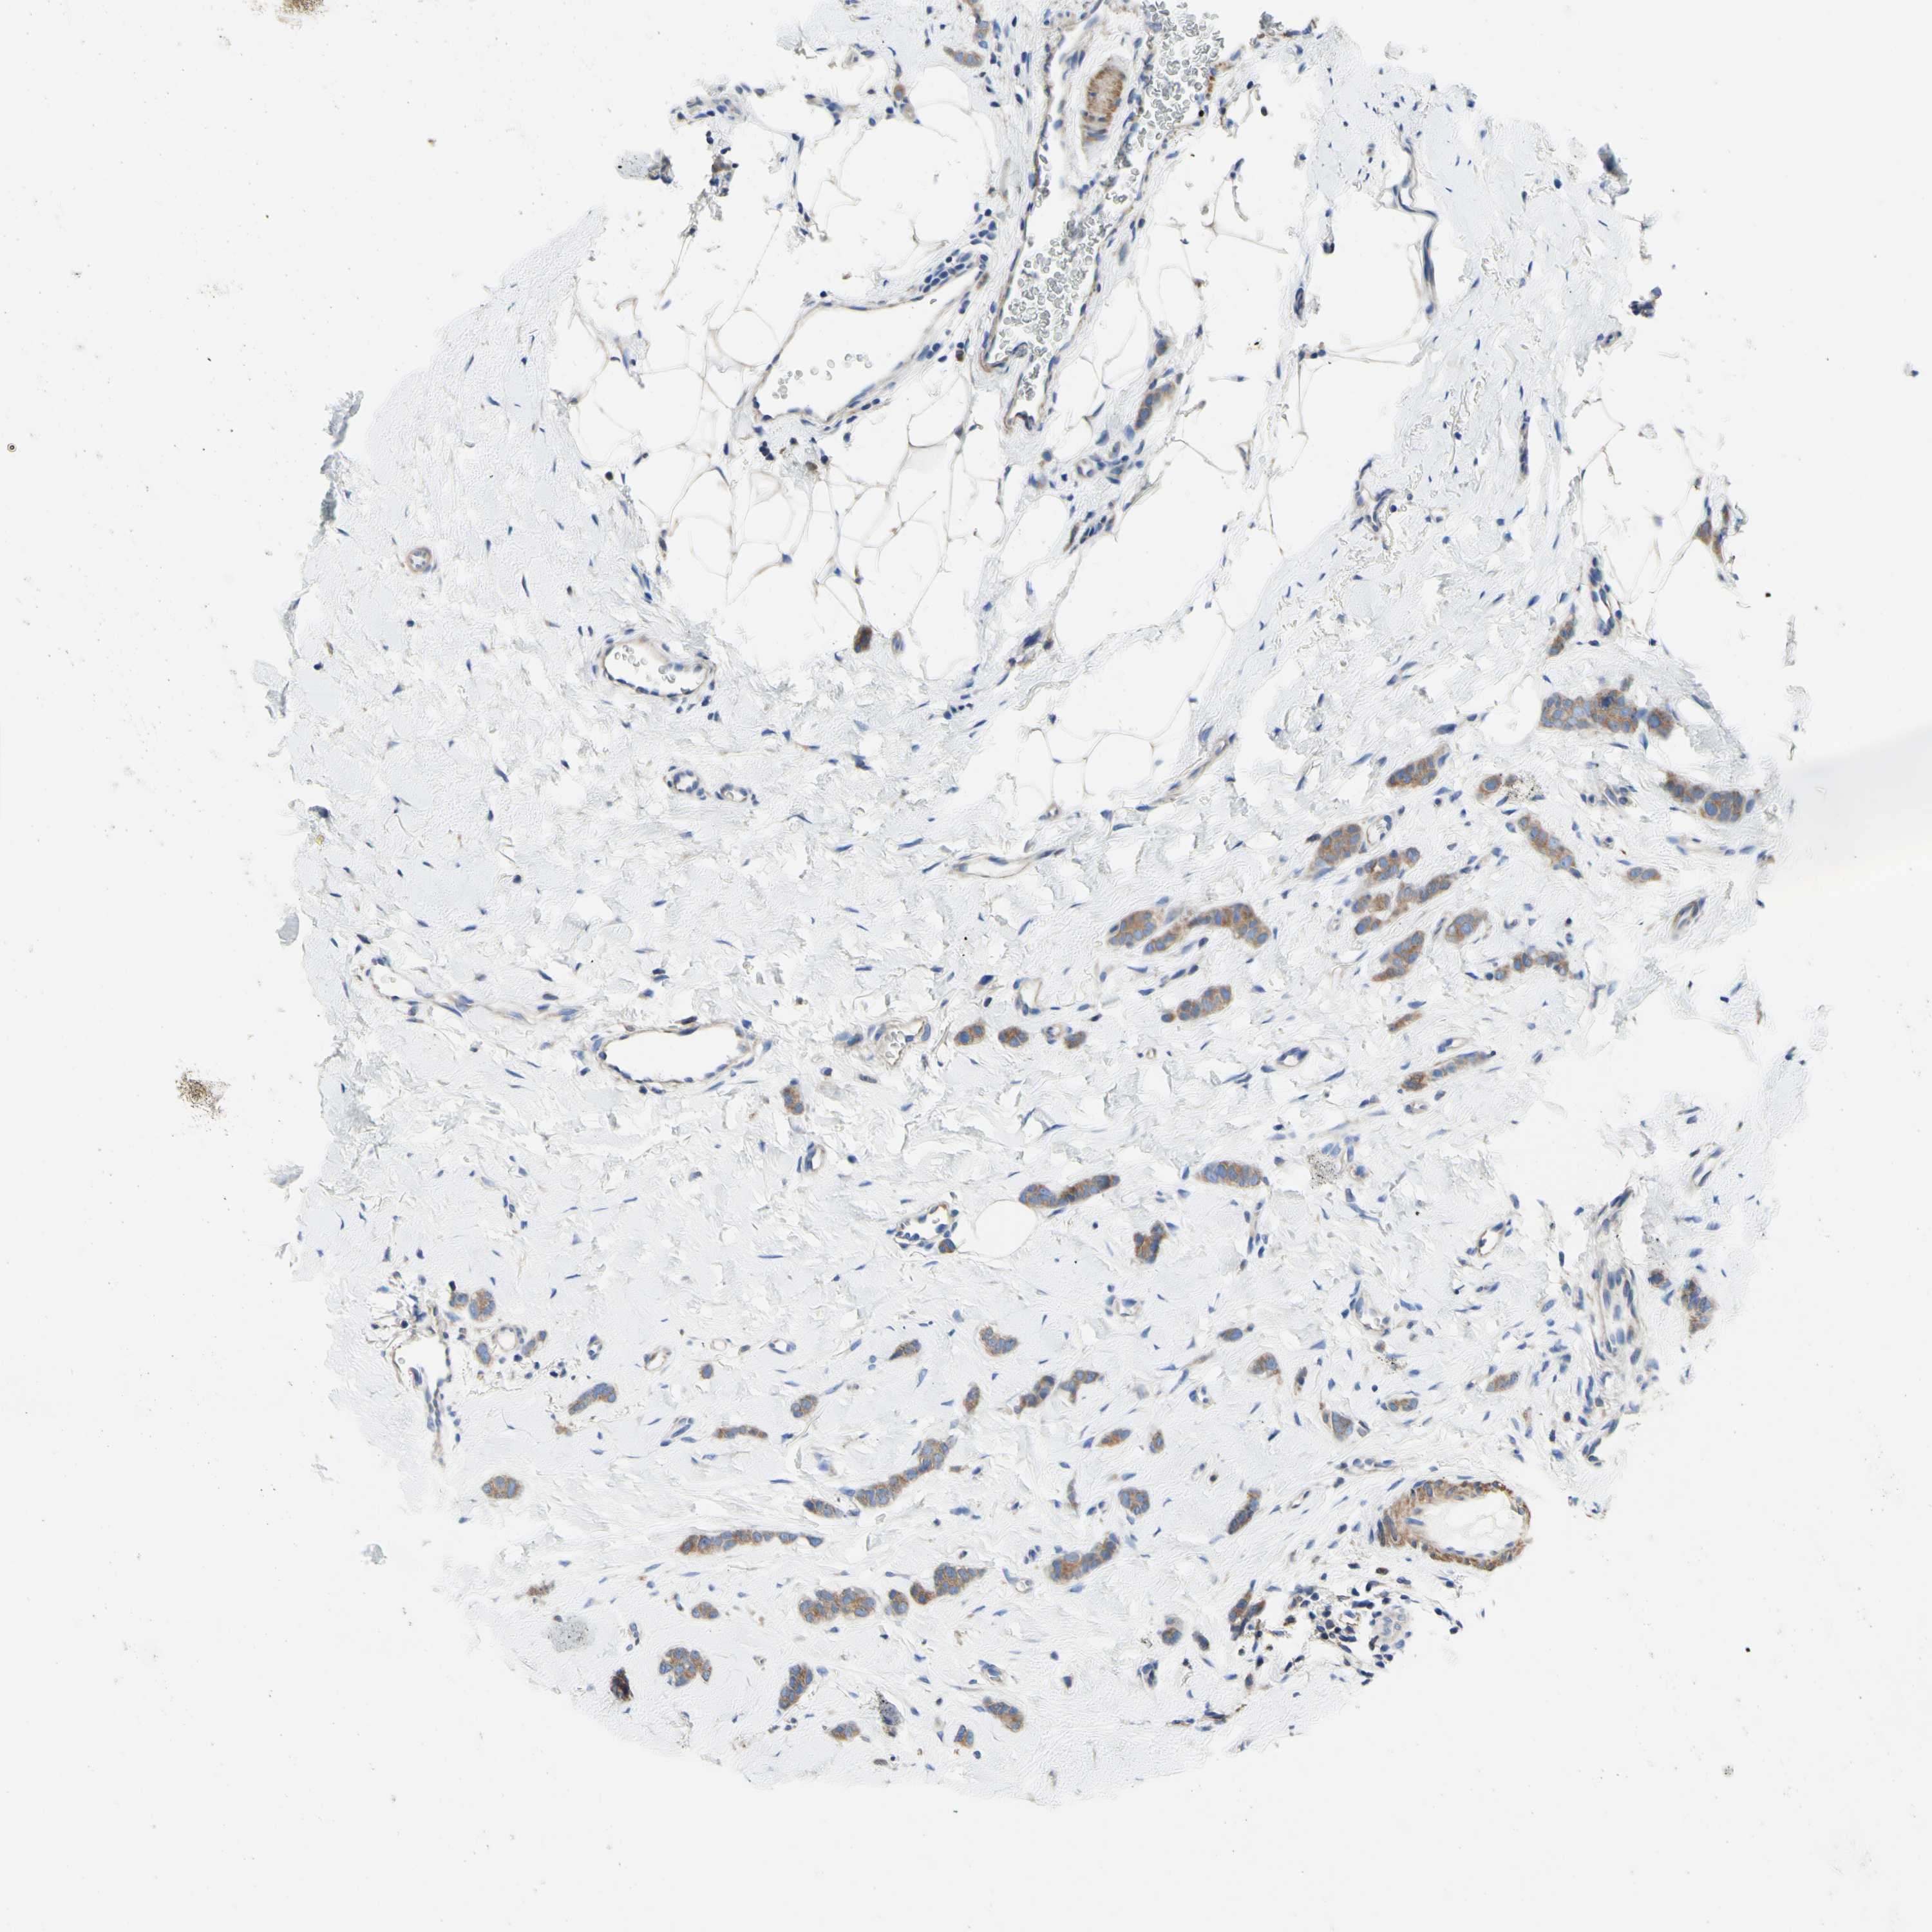

CANCER BREAST CANCER Show tissue menu

BRCA TCGA BRCA VALIDATION PROTEIN EXPRESSION